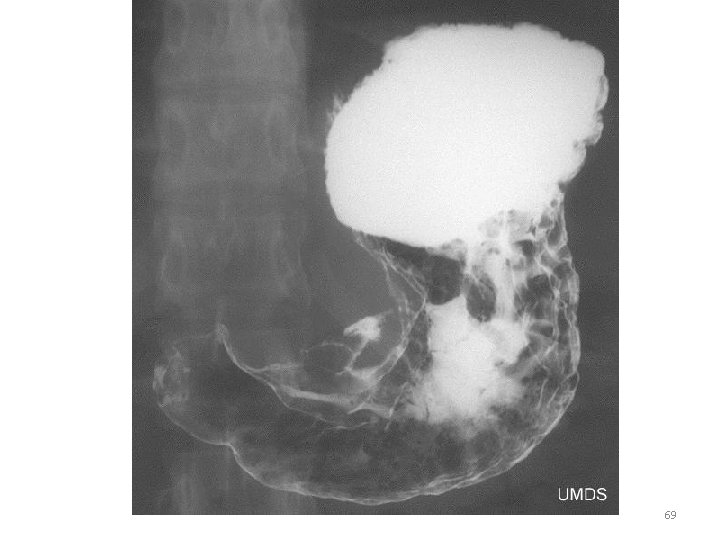

Flouroscopyxrays in motion 67

Fluoroscopy 68

69

70